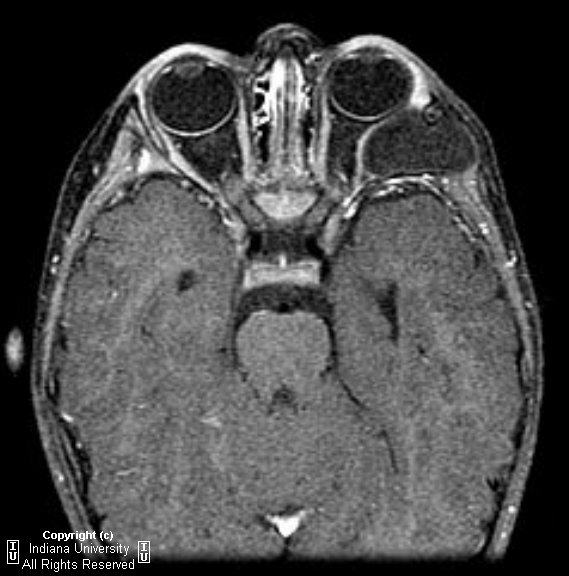

Carotid cavernous fistula

Diagnosis: Carotid cavernous fistula

Carotid Cavernous fistula (CCF) is a direct communication between the intracavernous portion of the carotid artery and the venous cavernous sinus. Usually is ipsilateral.

Clinical presentation: acute onset pulsating exophthalmos, orbital bruit, dilated conjunctival vessels, and glaucoma. No pain whereas psuedotumor is almost always associated with pain.

Unilateral diffuse enlargement of extra ocular muscles.

Proptosis.

Dilation of Superior ophthalmic vein (SOV) and venous structures within the carotid cavernous sinus due to backpressure. Our case was unusual in that the venous engorgement was on the opposite side of the CCF.

Irregularity of SOV may represent thrombus (not seen in this case).

Bowed convexity to the Cavernous sinus usually unilateral (our case demonstrated right cavernous sinus bowing due to the venous engorgement from the opposite carotid-very atypical)